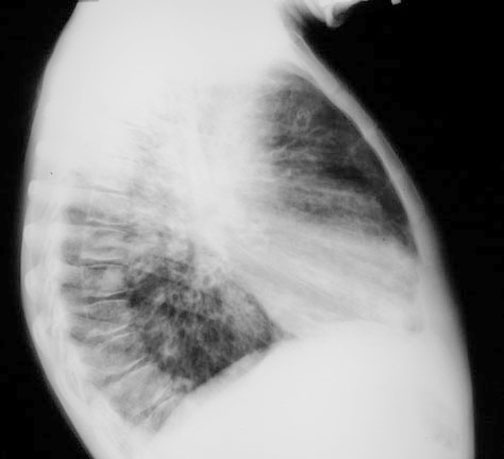

Case 4

Lateral